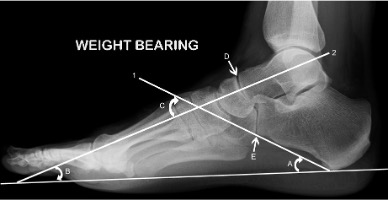

Lateral view

Line 1 = calcaneal inclination axis

Line 2 = midline axis of talus

A = calcaneal inclination angle

B = talar declination angle

C = lateral talocalcaneal angle

D & E indicate the cyma line

Calcaneal inclination axis

A line along the inferior surface of the calcaneus connecting the most inferior point of the calcaneal tuberosity with the most distal inferior point of the calcaneus at the calcaneo-cuboid joint.

Calcaneal inclination angle

Between the calcaneal inclination axis and the supporting surface, reflecting the height of the foot framework.

Measurements of 10-20° are considered low, 20-30° medium and >30° high. Angle varies with foot pronation or supination and clinical judgement is important.

Talar declination angle

Between a bisection through the body and neck of the talus and the supporting surface.

Normal: ~21°

Lateral talo-calcaneal angle

Between the calcaneal inclination axis and the midline axis of the talus.

Normal: 35-50°

The talo-navicular and calcaneo-cuboid joints together produce a superimposition on a lateral X-ray known as the cyma line. These curved joints together form a ‘lazy S’ as an intact curve in a normal foot. In a pronated foot the ‘S’ becomes broken as the talo-navicular joint moves anterior and plantar to the calcaneo-cuboid joint and the reverse occurs in a supinated foot